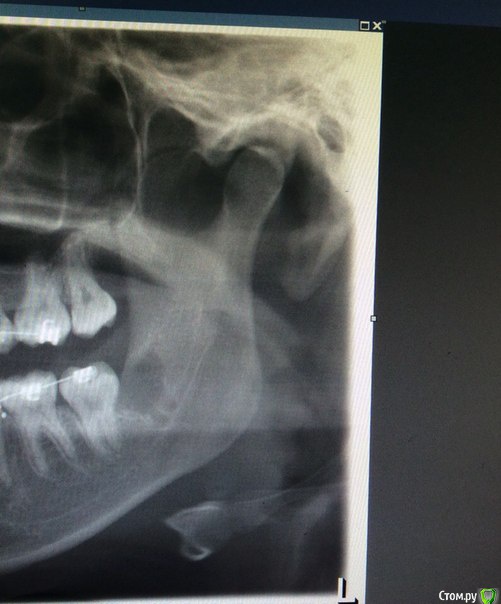

Янаyana Опубликовано 6 апреля, 2015 Поделиться Опубликовано 6 апреля, 2015 Подскажи пожалуйста мне 13 марта удалили последнюю восьмерку слева снизу.зуб был ретинированный. Удаляли полтора часа, но по удалению претензий нет.Лунка хорошо и быстро зажила, обезболивающие даже не понадобились.после удаления началась парастезия подбородка и левой части языка.подбородок прошел через 2 недели, как только сошел отек.но левая часть языка до сих пор онемевшая. Пропила пять дней мильгаму, результата не было. Врач назначил нейромультивит и хожу теперь на лазер.врач сказал, что тройничный нерв не поврежден, но воспален и пройдет все через полгода. Как только образуется костная ткань(если не ошибаюсь). Сходила к знакомому неврологу он сказал что повреждена маргинальная ветвь лицевого нерва, но в стоматологии уверяют, что эти вещи никак не связаны и что со всеми нервами все в порядке.можете ли по снимку определить поврежден ли нерв и какой или мне не о чем беспокоится?Может ли парастезия остаться навсегда или все таки пройдет?и может дадите пару советов. Ссылка на комментарий